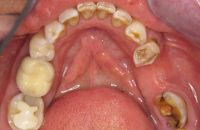

Voor de behandeling

Gebitsslijtage voornamelijk door knarsen. Aan de binnenkant zijn de tanden erg dun geworden en daardoor ook afgebroken. Door de diepe beet zijn de kiezen in onderkaak helemaal afgebroken.